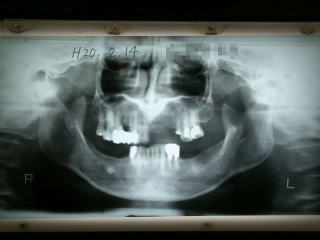

症例3

平成20年2月14日、初診のレントゲン写真